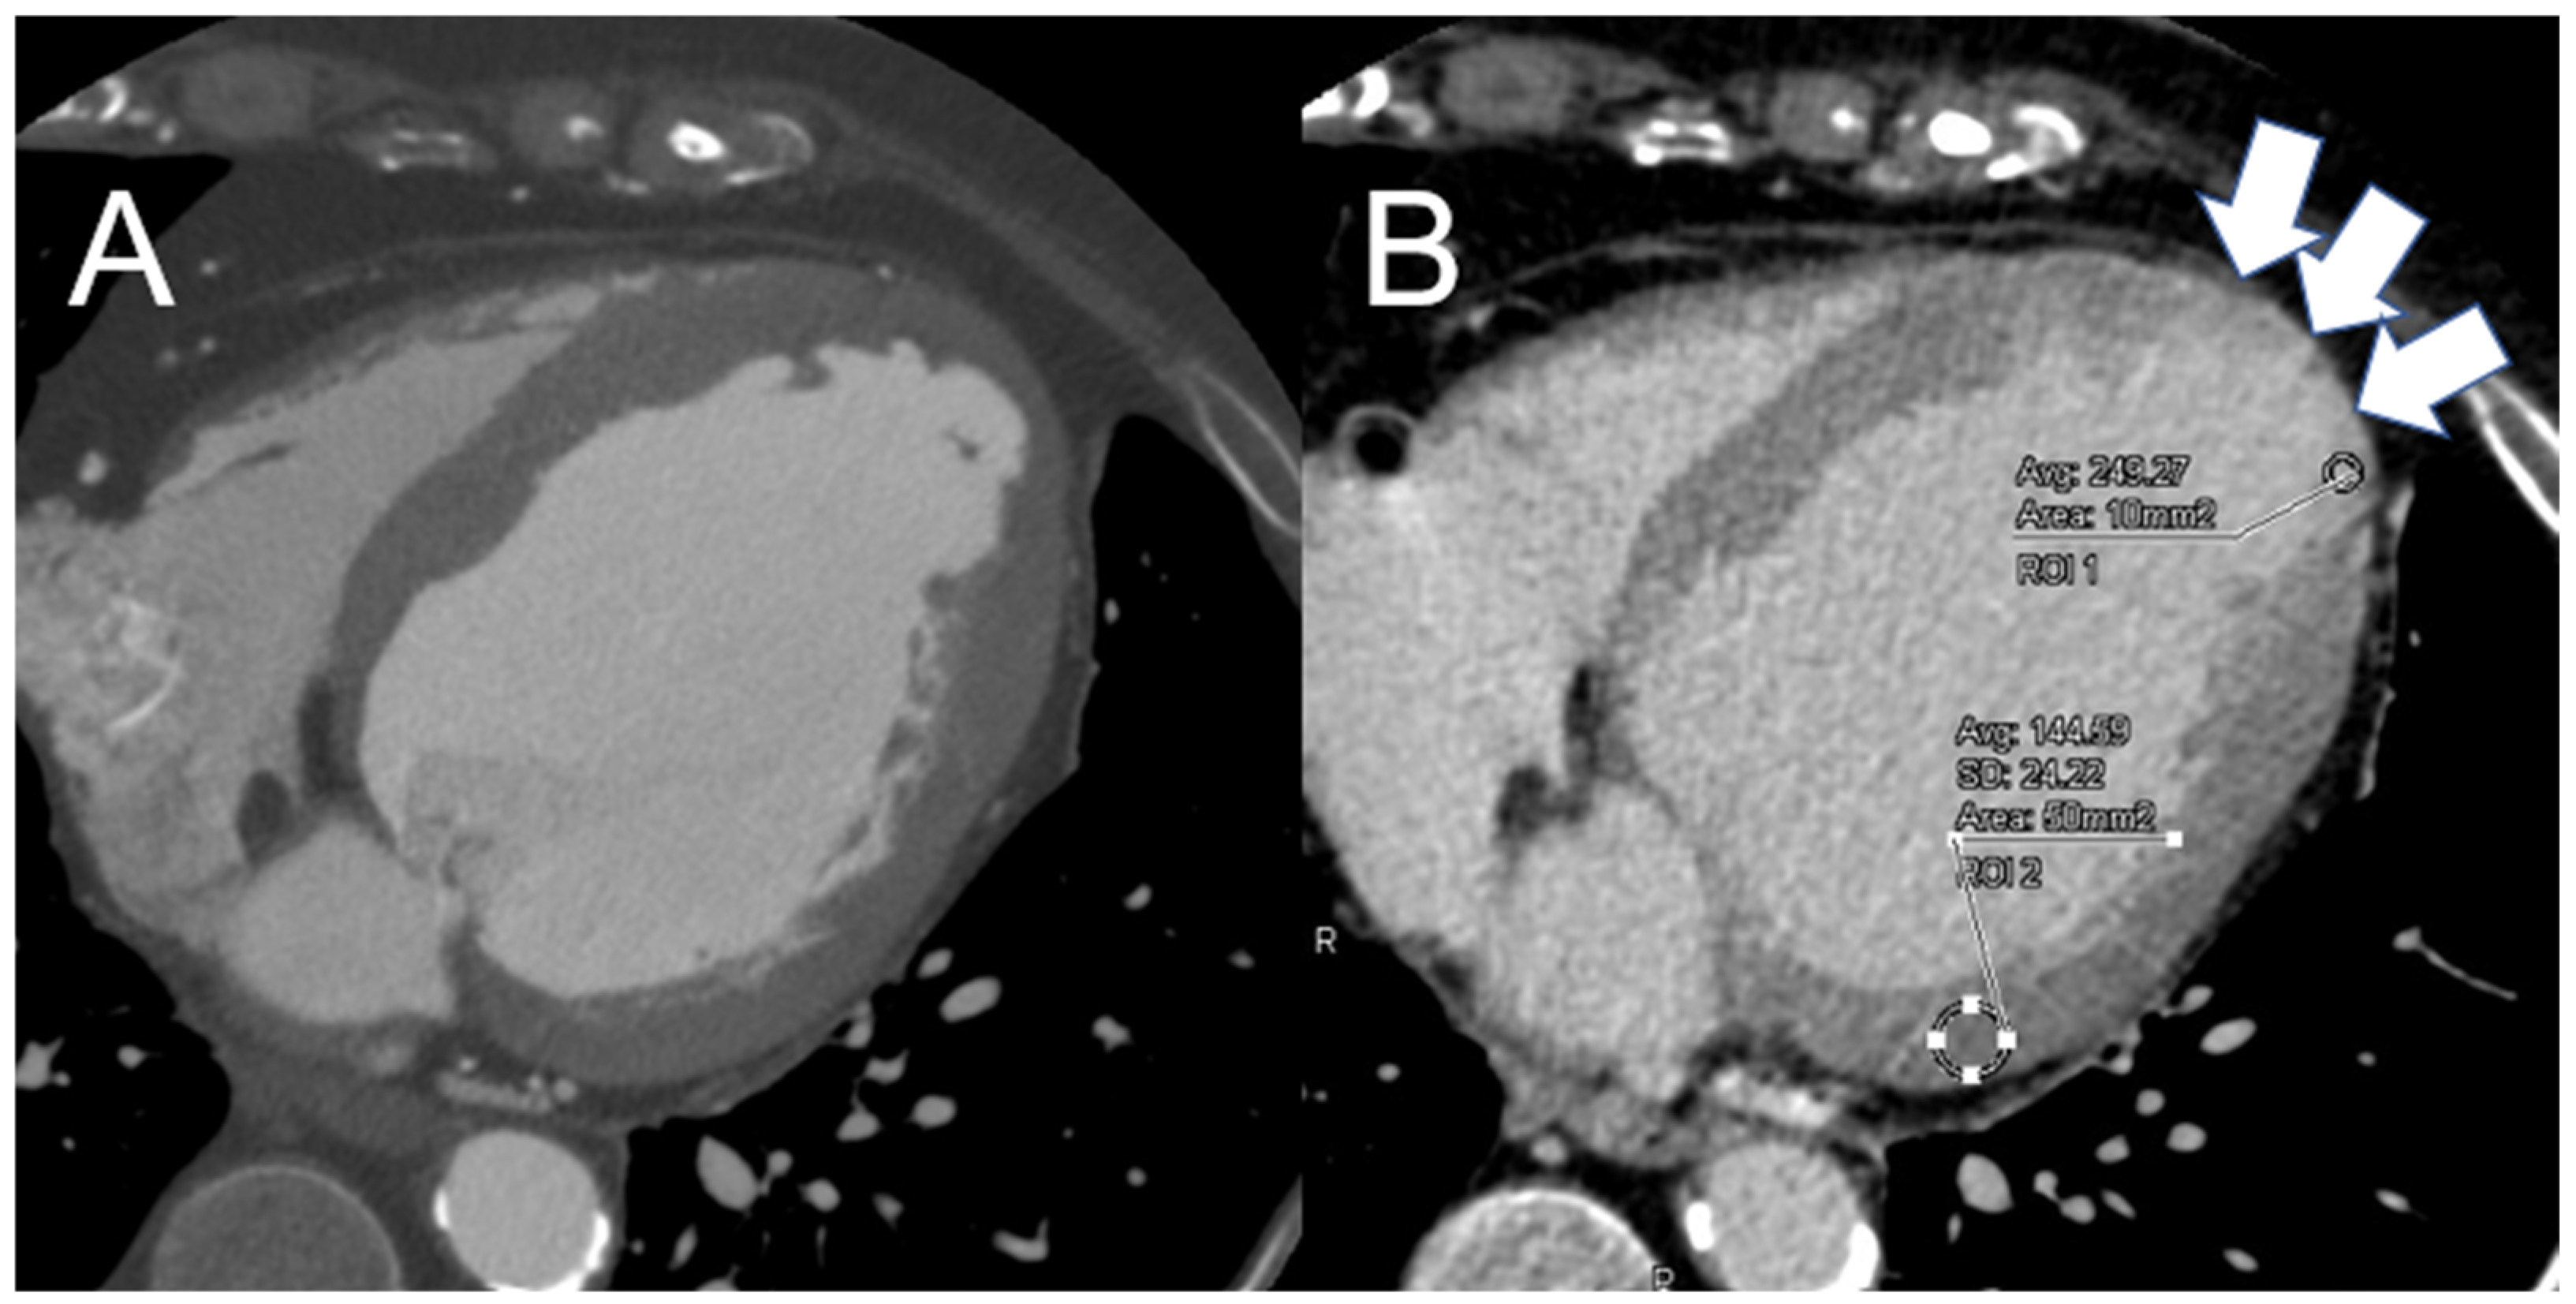

4.3. Improving Image Quality in Late-Phase Enhancement